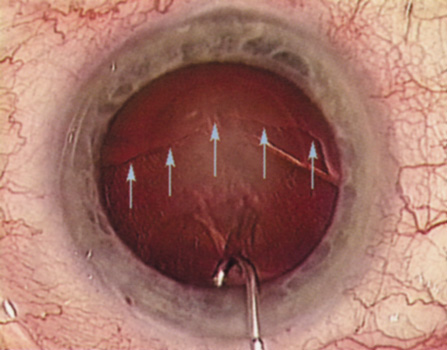

HYDRODISSECTION

Hydrodissection can be performed after the surgeon has successfully completed capsulorrhexis.97 If the capsulorrhexis is not intact, fluid forced around the interior of the capsule may cause the bag to splay open. With capsulorrhexis, hydrodissection is a safe and extremely useful maneuver. Hydrodissection can be thought of as two maneuvers: hydrodelineation and cortical cleaving hydrodissection. By placing a 27-gauge cannula on a syringe filled with balanced saline solution (BSS), the surgeon can direct fluid beneath the residual anterior capsular rim to create a cleavage plane. Depending on the direction the fluid wave takes, different lamellae of the cataract will be separated. Hydrodelineation is the term used when the cleavage plane separates the adult nucleus from the fetal nucleus or the adult nucleus from the more peripheral epinucleus. Hydrodelineation often results in the characteristic golden ring sign (Fig. 11). Cortical cleavage occurs when the cortex is separated from the capsular bag (Fig. 12). Finding the cortical cleavage plane may be facilitated by gently lifting the capsular margin away from the cortex with the BSS cannula before injecting. Several small bursts of fluid allow the surgeon to monitor progress of the fluid wave. When dealing with a soft nucleus, the authors strive to perform true cortical cleaving hydrodissection. For a hard nucleus, hydrodelineation allows manipulation of less of the nuclear bulk, although the remaining epinuclear shell must be addressed in an additional step. Hydrodelineation is particularly useful if the nucleus is not freely mobile after cortical cleaving hydrodissection.

Fig. 11. A crisp “golden ring” is seen from the fluid cleft between the epinucleus and nucleus with hydrodelineation.

Fig. 12. Hydrodissection, performed subincisionally with a 27-gauge J-cannula, produces a cleavage plane between the capsule and the cortex. The small blue arrows indicate the advancing fluid wave.